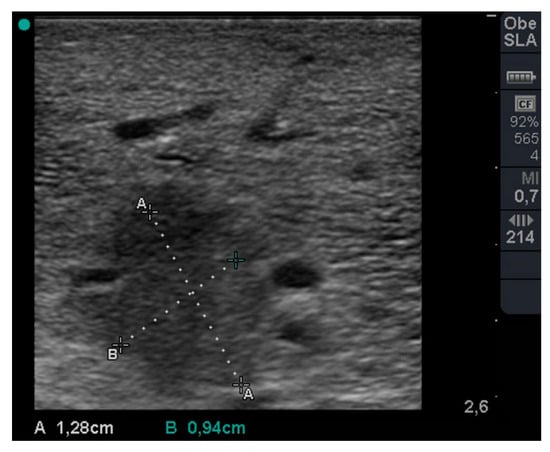

During stable flooding in-vivo with saline, unimpaired imaging without remaining air was achieved. The lung parenchyma appears homogeneous with enhanced echogenicity, where vessels and bronchi are well demarked as hypoechoic structures [18]. Trans-pulmonary imaging visualized adjacent organs such as the liver or heart (Figure 4). Doppler imaging in flooded lung is feasible and useful to detect vessels (Figure 5). No limitations regarding penetration depth were documented. High frequency linear probes (10–15 MHz) were recommended for high resolution imaging such as for small bronchi or vessels [22] (Figure 6). Using ex-vivo models and simulated intra-pulmonary nodules in-vivo, a reliable nodule detection of primary lung cancer as well as metastases were found. The tumor mass appears hypoechoic, surrounded by hyperechoic flooded lung, resulting in a high detection rate of about 100% of malignant pulmonary nodules (Figure 7), as well as simulated nodules [31]. Interestingly, the visualization is aggravated only for the bronchoalveolar cell carcinoma. The specific growth along the alveolar surface caused an echo-enhanced appearance with similar characteristics to flooded lung parenchyma [18].

Figure 6. Sonographic imaging of hypoechoic Non-Small-Cell Lung Carcinoma (NSCLC) in saline flooded lung using ex-vivo human lung models (With permission from Lesser et al. [18]).